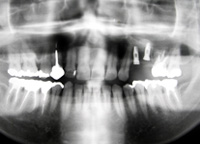

STEP3 精密検査

インプラント治療が有力候補である場合は精密検査を行います。

検査内容はCT・レントゲン撮影・模型作成等を行います。